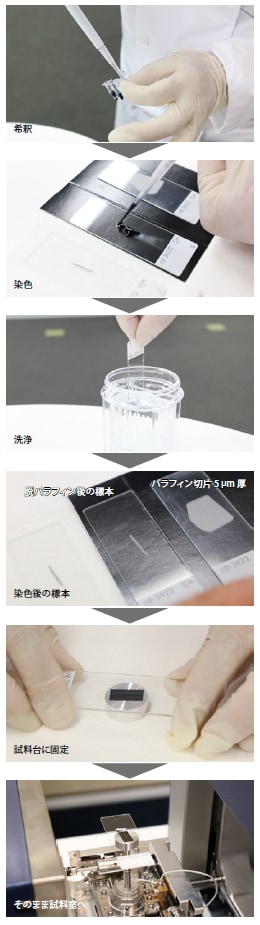

使用Platinum-blue分染病理组织

稻贺教授充分发挥低真空SEM的优势。肾穿刺的应用源于染色剂的出现。“我认为Platinum-blue染色剂将成为未来发展的关键。”当时电子染色剂乙酸铀酰较为普遍,但随着国家对于乙酸铀酰的限制越来越严格,人们开始寻找替代品,于是Platinum-blue逐渐被业界人士关注。但是,市售的Platinum-blue染色剂对使用人群有所限制。为了解决这一问题,田中教授研发了Platinum-blue作为低真空SEM信号增强剂,稻贺教授巧妙设计了辅助操作的小配件。这两款产品和TEM染色剂同时投放市场,开始逐步普及。老鼠舌头上有多种组织,故本次实验取老鼠舌头局部用于制备样品切片。后经实验证实,Platinum-blue染色剂可清晰分染几种病理组织,这一发现我们也曾在学会上做过相关报告。

通过电子显微镜分析样品切片

“将标本置于载玻片上,然后放入样品仓内,由于低真空特性我们可以清晰观察到标本。我认为低真空SEM的应用是电镜历史上的伟大创举。如今,任何人均可通过电子显微镜观察常见标本、光学显微镜标本等。”

PAM染色是一种光学显微镜样品染色法,采用银染法使组织切片着色,将这种方法和Platinum-blue染色法有机地结合起来,可进一步提升分析的准确性。

稻贺教授谈到,“PAM染色法可分染基底膜,使组织结构清晰,这种染色方式和Platinum-blue截然相反,所以我们联用这两种染色法,优势互补,染色结果非常不错”。“而且PAM染色具有悠久的历史,经山中教授课题组的矢岛老师改良,操作现在变得十分简单。PAM染色和Platinum-blue染色的有机结合,对当今时代的肾病诊断具有重要的意义。从同一组织内取两个标本,可通过PAM染色法和Platinum-blue染色法,全面观察组织结构,对病理进行深入诊断。”